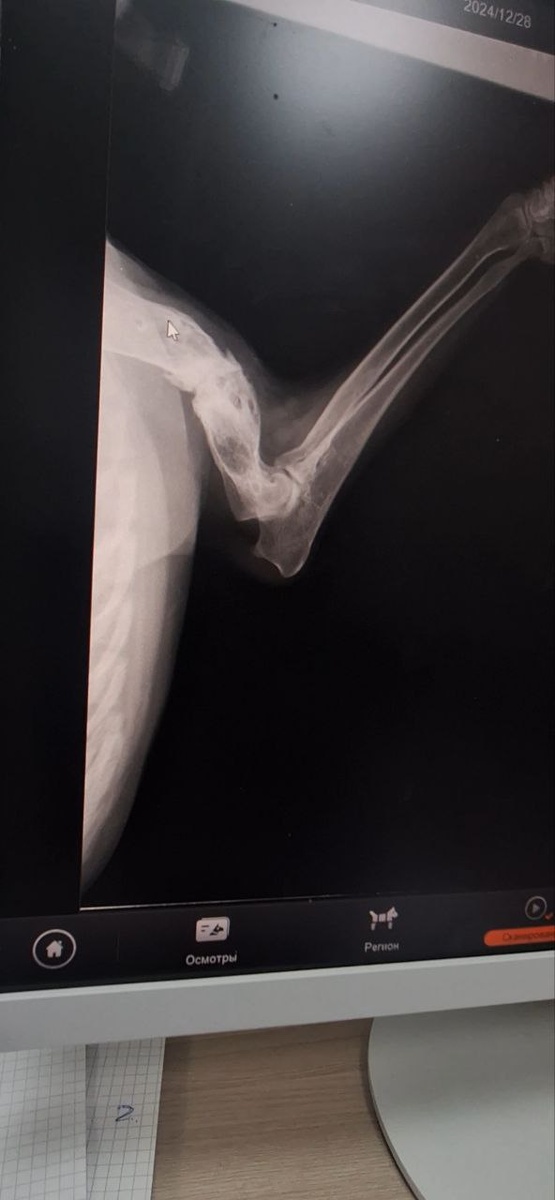

Едем домой. Спасибо, рентген оплатила 🤝Новости скоро напишу.